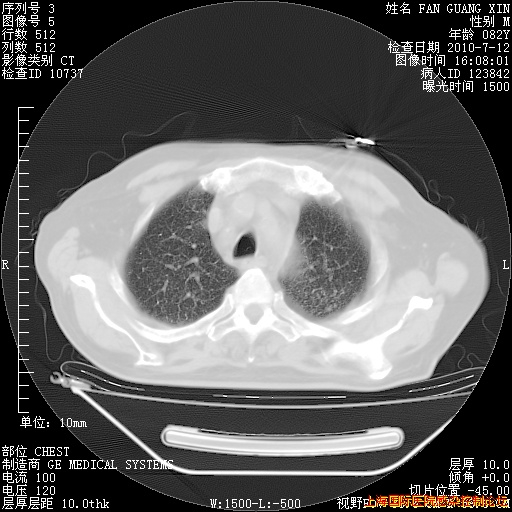

补发6月12日肺部CT肺窗

6月12日肺窗

今天复查CT

整整相隔30天的肺部CT好像有所好转啊。甲强龙减量第3天,需要观察体温。

海管,自昨日你和我通完话后,不知您岳父消化道症状有无缓解?体温怎样?阅读7.12日胸部ct,个人认为目前激素治疗是有效的,甲强龙减量是适宜的。因在抗痨治疗,需密切观察肝功、肾功能和血常规。不过,老年、长期住院和大量使用激素,很担心菌群失调发生